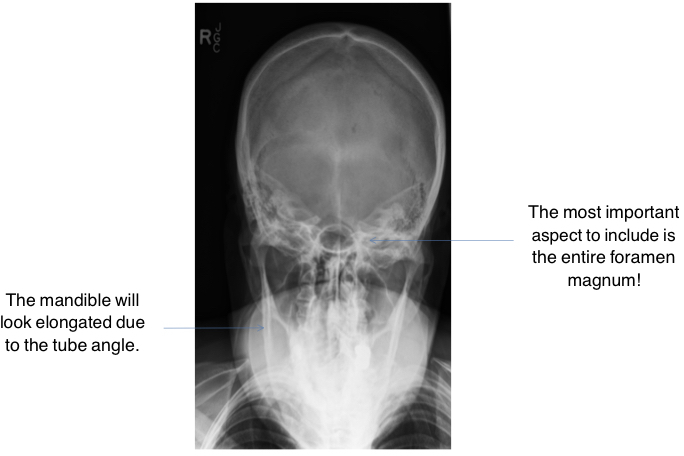

AP Axial - Towne Method

The patient is in the ___ position (or sitting on chair).

Adjust the patient’s head so that the ___ ___ is ___ to the IR.

Flex the ___ enough to place the ___ perpendicular to the IR.

Direct the CR though the ___ ___ at a ___ angle of ___° to the ___ or ___° to the ___, so the CR enters approximately ___ inches above the ___.

Position the IR so that its ___ edge is at the level of the ___.

This projection is taken to demonstrate the ___ bone. The entire ___ ___ must be included.

The patient is in the supine position (or sitting on chair).

Adjust the patient’s head so that the midsagittal plane is perpendicular to the IR.

Flex the neck enough to place the OML perpendicular to the IR.

Direct the CR though the foramen magnum at a caudal angle of 30° to the OML or 37° to the IOML, so the CR enters approximately 2.5 inches above the glabella.

Position the IR so that its upper edge is at the level of the vertex.

This projection is taken to demonstrate the occipital bone. The entire foramen magnum must be included.